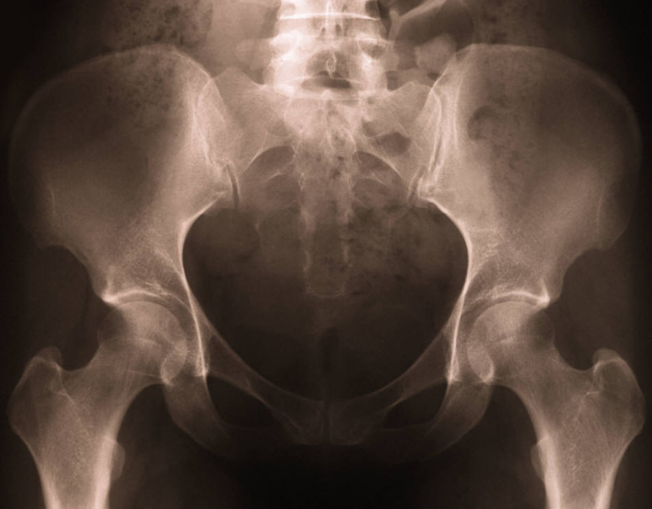

Enquadramento: A coxartrose é importante fonte de morbilidade. Para o diagnóstico de coxartrose em paciente com coxalgia, geralmente é realizada uma radiografia pélvica, sendo considerado esse diagnóstico perante evidência radiográfica.

Desenho do estudo: Estudo de teste diagnóstico. Os autores avaliaram dados provenientes de dois estudos de coorte norte americanos:o “Framingham Osteoarthritis Study” (FOS) e o “Osteoarthritis Iniative” (OI). Do FOS foram avaliadas 946 pessoas com idade ≥ 50 anos. Recorrendo a uma representação visual os indivíduos foram questionados quanto à presença de dor (na maioria dos dias) e sua localização. Os que responderam afirmativamente foram submetidos a manobra de rotação interna passiva e palpação da região trocantérica. Da coorte OI foram recrutadas 4796 pessoas, entre os 45 e os 79 anos de 4 cidades diferentes. Foi utilizada uma representação visual dos locais onde comummente é reportada a dor na coxartrose. Os investigadores perguntaram se existia dor ou rigidez em alguma daquelas localizações na maioria dos dias de um mês no último ano. Todos os participantes das duas coortes foram submetidos a radiografia pélvica (teste diagnóstico). O gold standard utilizado foi clínico. Foi analisada a concordância entre dor e alterações radiográficas e, para aqueles com dor sugestiva de coxartrose, foi calculada sensibilidade, especificidade, valor preditivo positivo e valor preditivo negativo da radiografia pélvica como teste diagnóstico.

Resultados: Do estudo FOS, apenas 15,6% dos pacientes com coxalgia apresentaram evidência radiográfica de coxartrose e apenas 20,7% dos que tinham alterações radiográficas características de coxartrose referiram dor. Da outra coorte (estudo OI), os resultados foram 9,1% e 23,8%, respetivamente. O exame radiográfico apresentou especificidade de 90,9% e 94,3% e valor preditivo negativo de 87,6% e 84,1%, respetivamente na primeira e segunda coortes analisadas. Os valores de cada teste foram também calculados relativamente a dor referida a diferentes localizações ou, no caso da coorte FOS, à combinação com a manobra de rotação interna, sendo a dor na virilha o que apresentou maior sensibilidade (36,7% e 16,5%, respetivamente).